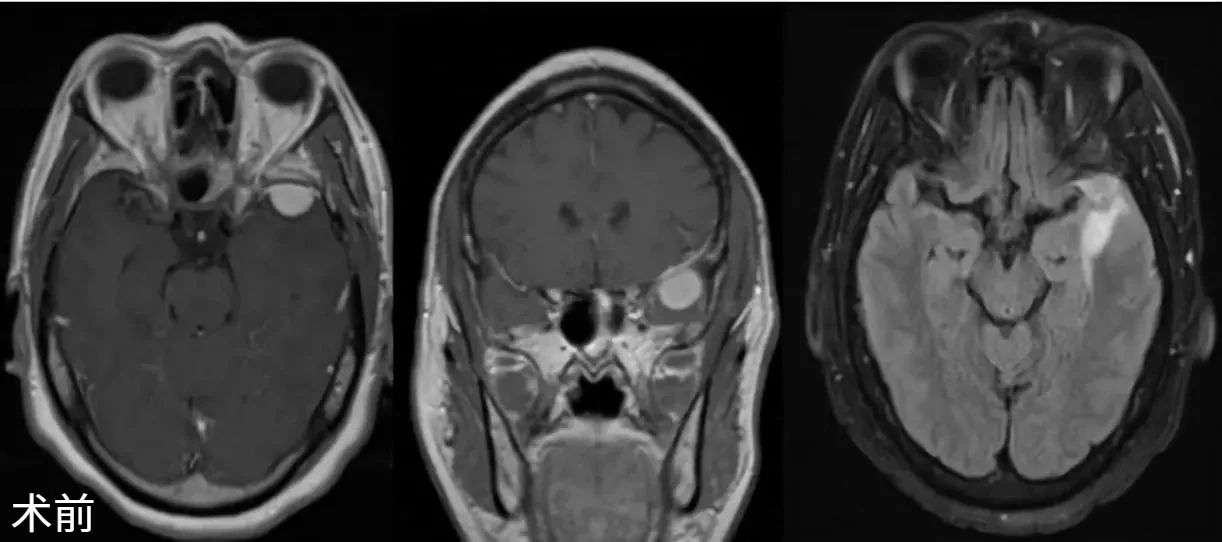

1例以癫痫起病的56岁男性患者,MRI提示左蝶骨嵴内侧1/3脑膜瘤。采用改良眉弓切口扩大眶上入路,Simpson II级切除肿瘤。创伤小,兼具较好的美容效果(图2、3、4)。

图3. MRI显示蝶骨嵴内侧脑膜瘤,术前、术后成像。